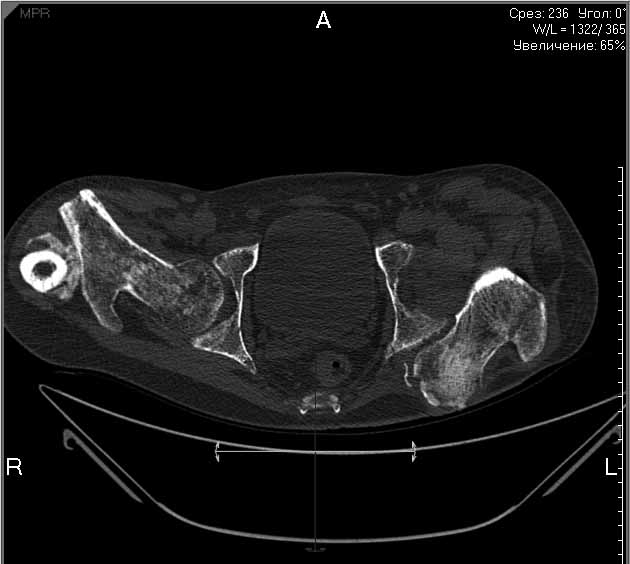

На лечении находится пациент с тяжелой сочетанной травмой. На сегодняшний день встал вопрос о тактике лечения переломов бедер( по месту жительства бедрами не занимались).

Пациенту 22 года. Травма в июле 2010г, лечился в районной больнице. К нам попал в апреле 2011г. Тяжелая сочетанная травма (29.07.2010): тупая травма живота с повреждением внутренних органов. Закрытая травма грудной клетки с переломом ребер. Пневмоторакс справа. Тяжёлая позвоночно-спинномозговая травма. Закрытый осложнённый переломо-вывих С5 позвонка. Верхний парапарез, нижняя параплегия, нарушение функции тазовых органов по типу недержания. Цекостома. Пролежень левой ягодичной области. Неправильно консолидированные переломы верхних третей обеих бедер. Застарелый вывих левого бедра. Осложнение: Поддиафрагамльный абсесс слева, забрюшинного пространства. Свищ желудка и ободочной кишки. Синегнойный сепсис. Двухстороняя пневмония. Но это уже анамнез. Пациент был неоднократно оперирован на органах брюшной полости и осложнениями с ними связанными.

В ягодичной области слева глубокий пролежень размером 2х2см, дном является вывихнутая головка бедра. Неврологически в нижних конечностях динамика положительная, появились движения в правой стопе, чувствительность в стопах. По переломам бедер: подвижности в местах переломов нет, снимки высылаю.

Уважаемые коллеги, помогите определиться с оптимальной тактикой в лечении перелома бедер. Степень оснащенности у нас достаточная (аппараты, штифты, пластины, ЭОП).

Планирую начать с правого бедра, ЧКО таза (передняя рама) с фиксацией бедра. О/клазия места перелома правого бедра и устранение грубых смещений в аппарате. окончательно можно оставить и в аппарате. Далее аппаратное устранение вывиха левого бедра.